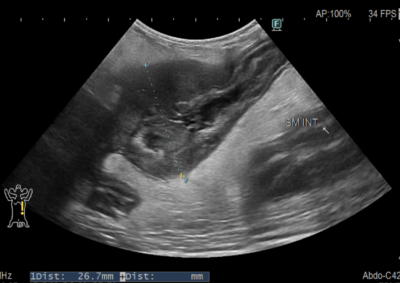

軟部組織外科 注意 ボタンをクリックした先に、治療中および手術中の画像が説明で使用されている場合がございます。 そのような画像に弱い方は閲覧なさらないようお願いいたします。 軟部組織外科救急・集中治療 胆嚢粘液嚢腫破裂 軟部組織外科腫瘍外科 膵臓腫瘍による肝外胆管閉塞 軟部組織外科救急・集中治療 肝葉捻転 軟部組織外科救急・集中治療 尿道腫瘍・膀胱瘻チューブ設置 軟部組織外科 経恥骨骨切り尿道瘻設置術 救急・集中治療軟部組織外科 猫の子宮蓄膿症 軟部組織外科 猫の直腸脱 軟部組織外科救急・集中治療 猫の腸閉塞(毛玉) 軟部組織外科救急・集中治療 小腸腫瘍壊死による細菌性腹膜炎 軟部組織外科救急・集中治療 異物による十二指腸穿孔・細菌性腹膜炎 軟部組織外科 腸閉塞・腸切開 軟部組織外科救急・集中治療 犬の胆嚢粘液嚢腫破裂 <123456789> 症例カテゴリー 放射線治療整形外科軟部組織外科脳神経外科内科腫瘍外科救急・集中治療リハビリテーション科腫瘍内科内視鏡科脳神経科呼吸器外科中医・漢方猫の腎移植循環器科